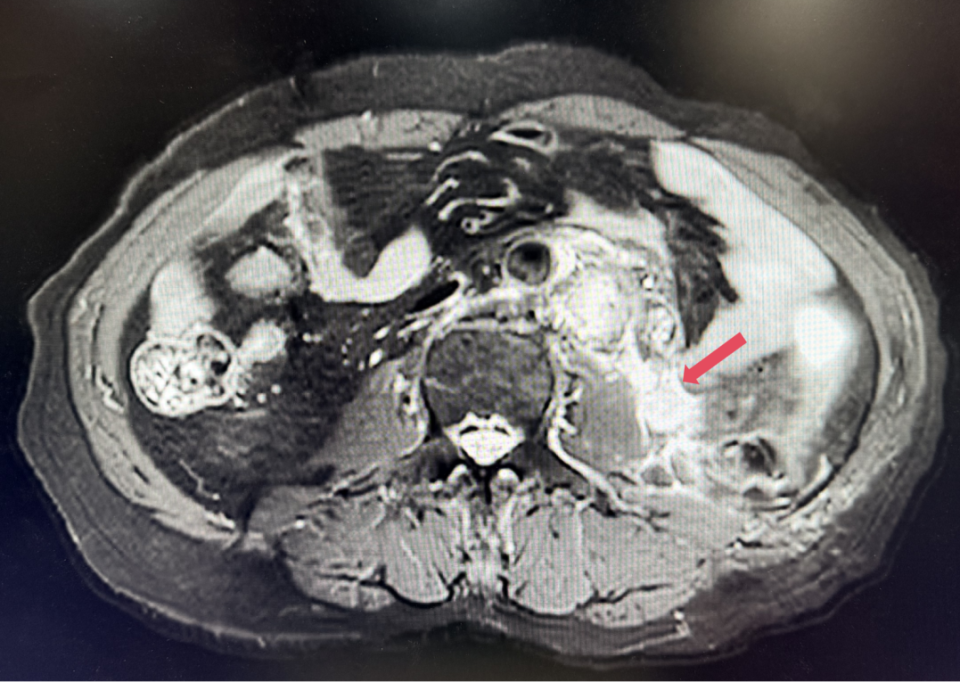

2023年11月,最深应答

2023年11月:治疗10个月(C15)评估,肿瘤负荷减少至41mm,维持PR。

患者初诊时68岁,2020年9月因“体检发现左肾占位2年”行腹腔镜下左肾根治性切除术,术后病理提示为肾透明细胞癌,pT3aN0M0,未行术后辅助治疗、未规律复查。2022年3月胸腹盆CT示腹膜后转移,IMDC评分0分,低危组。随后予一线培唑帕尼治疗,最佳疗效SD,2022年11月PD。于2023年1月经筛选进入Ⅲ期FRUSICA-2临床研究,开始接受呋喹替尼联合信迪利单抗二线治疗,用药6周(C2)后首次肿评即实现疗效PR(缩瘤率40.2%),用药10个月时缩瘤率近七成(68%),并维持上述水平至今,PFS已经超过37个月,在二线治疗中实现了长期无进展生存。同时,患者对呋喹替尼联合信迪利单抗方案耐受性良好,仅见轻微蛋白尿和偶然腹泻,未见其他不良反应,也未见免疫治疗相关不良反应。该方案有望为TKI经治的晚期肾癌患者带来新的选择,为实现长期生存提供可能性。